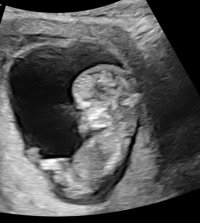

Har disse, men tror ikke nub viser herSyns dette ser veldig ut som en gutt, pga det «laget» oppå + at den går oppover. Men har du noen flere bilder?![]()

Siste bilde så kan se se ut som en guttHar disse, men tror ikke nub viser her